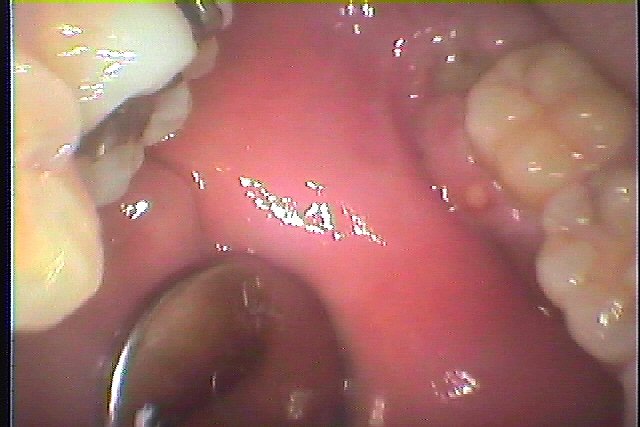

ブログ一覧|広島市安佐南区の歯科医院 ブログ一覧 トップ ブログ一覧 お知らせ スタッフブログ ブログ一覧 お知らせ 2025/01/10 右の口角部の良性腫瘍 レーザーにて切除を行っていきます お知らせ 2025/01/10 右上の1番部が真横に生えてきた 診てほしい 過剰市が原因で歯列不正を起こしていました お知らせ 2025/01/09 右下の奥の親不知の難抜歯 こういう歯はまっすぐ生えていて抜きやすい歯になります お知らせ 2025/01/09 右下の奥の親不知の難抜歯 このような歯が超最難関といえます お知らせ 2025/01/08 左下の親不知の水平埋伏歯の難抜歯 ずっと抜きたいと思っていた お知らせ 2025/01/08 左下の奥 埋まっている親知らずの難抜歯 時々歯茎が腫れたり、いつも違和感がある お知らせ 2025/01/07 左下の奥に違和感が主訴にて来院 よく違和感が出るそうです お知らせ 2025/01/07 右上奥の完全埋伏歯の難抜歯 毎回よく歯茎が腫れるそうです << 1 2 3 4 5 … 10 11 12 13 14 … 870 871 872 873 874 >> Web診療予約 初めての方へ 選ばれ続ける理由 院内設備について 歯が痛いしみる一般歯科 歯がぐらぐらする歯周病 健康な歯を保ちたい予防歯科 子供の虫歯予防をしたい小児歯科 銀歯をセラミックに審美歯科 白い歯を目指しませんか?ホワイトニング 矯正専門医がいるので安心矯正歯科 抜けた歯を補いたいインプラント・入れ歯 医院案内 スタッフ紹介 メリィハウス歯科クリニックオフィシャルホームページ ラベンダー歯科クリニックオフィシャルホームページ お知らせ・ブログ ホーム 診療科目 一般歯科 歯周病治療 予防治療 小児歯科 審美治療 ホワイトニング 矯正歯科 入れ歯・インプラント マウスピース矯正 初めての方へ 院長・スタッフ 設備紹介 医院案内・アクセス メニューを閉じる